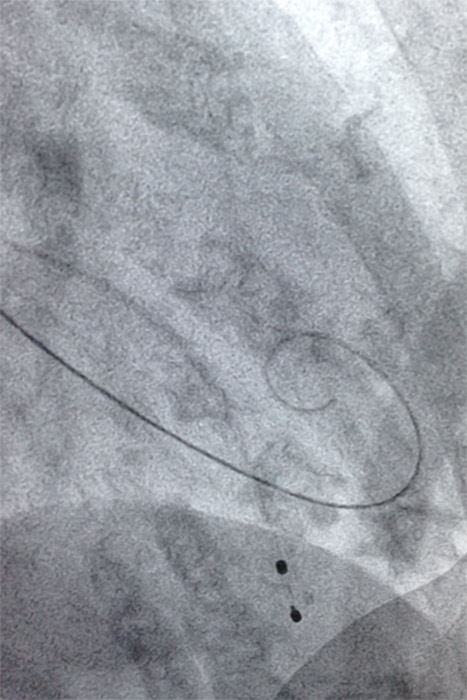

The INNOWI® wires have three independent zones of stiffness providing optimal support. The ultra-stiff proximal portion of the wires facilitates easy advancing of the introducer sheath and superior pushability and maneuverability. INNOWI‘s extra-stiff, respectively INNOWI SX‘s superstiff distal portion adapts perfectly to the anatomy in the aortic arch and provides sufficient guidance and support for the valve introducer system. The Pig-Tail-Tip allows atraumatic positioning in the ventricle, thereby protecting the heart muscle during the implantation of the valve.

The smooth transition from the stiff wire to the flexible tip facilitates atraumatic vessel navigation.